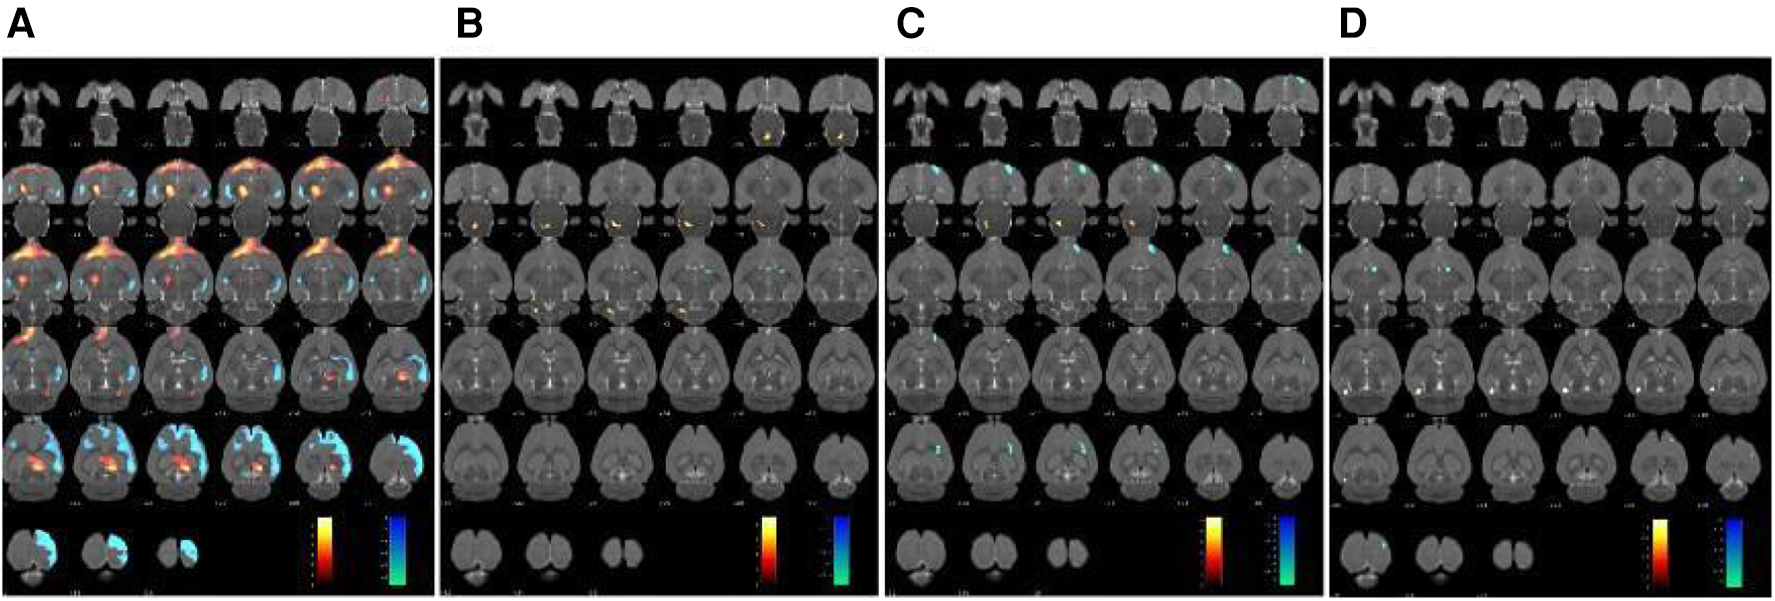

The changes in cerebral glucose metabolism in the SHRs brain were investigated. Compared to the WKY group, the SHR group exhibited a significant increase in glucose metabolism in the dorsal thalamus, dorsal thalamus lateral nucleus group, hypothalamus, lateral prefrontal cortex, and prefrontal cortex. However, other cerebral regions, including the sensory cortex, caudate putamen, olfactory Bulb, and visual cortex, showed a decrease in glucose metabolism (Table 2 and Figure 2A). In contrast, compared to the SHR group, the EA group showed a significant reduction in glucose metabolism in the dorsal thalamus, dorsal thalamus lateral nucleus group, and hypothalamus, while the cerebellum anterior lobe, medulla oblongata, and cerebellum posterior lobe exhibited a significant increase in glucose metabolism (Table 3 and Figure 2B). Furthermore, compared to the SHR group, the Sham-EA group displayed a significant decrease in glucose metabolism in the thalamus, medulla oblongata, and pontine tegmentum of pons, while the sensory cortex and caudate putamen showed an increase in glucose metabolism (Table 4 and Figure 2C). Finally, the EA group was compared with the Sham-EA group. The results showed that, compared to the Sham-EA group, EA downregulated the glucose metabolism in the hypothalamus, basal ganglia, and striatum, while the glucose metabolism in the corpus callosum, cerebellar hemisphere, hippocampus, and some cortical tissues was upregulated by EA (Table 5 and Figure 2D).

Figure 2

Glucose metabolism in the brain region was scanned after 7 days of treatment. The results were superimposed onto axial perspectives of the rat brain and aligned with the Paxinos and Watson rat brain atlas. (A) SHR group compared with the WKY group, n = 10. (B) EA group compared with the SHR group, n = 10. (C) Sham-EA group compared with the SHR group, n = 10. (D) EA group compared with Sham-EA group, n = 10. The color scale corresponds to the t-values observed for each significant voxel, where warm colors represent up-regulation of glucose metabolism, and cool colors represent down-regulation of glucose metabolism.